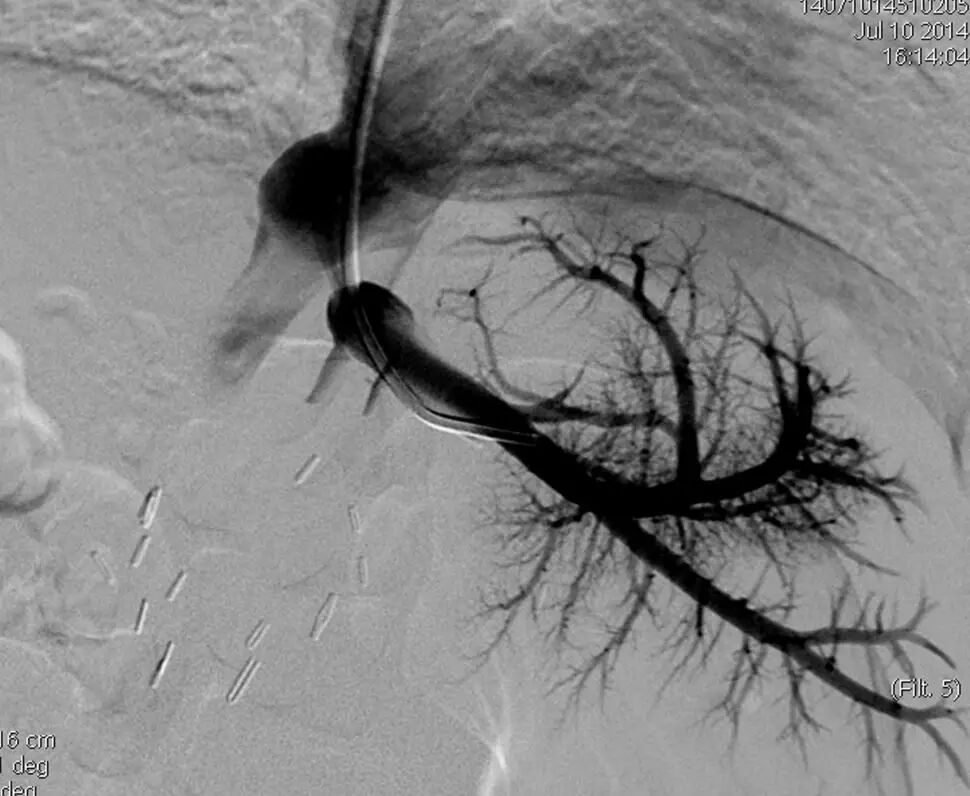

与上述无创性检查方法相比,血管造影是诊断HVOO的金标准和进行血管腔内介入治疗的依据多数学者主张在彩色多普勒超声诊断提示或临床诊断怀疑有HVOO应立即行腔静脉造影以明确诊断

4  HVOO介入治疗

HVOO的主要治疗方式有药物(肝素、香豆类抗凝药、尿激酶等)、手术(静脉分流、重新吻合静脉、再次肝脏移植)及血管腔内介入治疗(包括球囊扩张成形术、血管支架成形术)。对于术后患儿,梗阻多为血管扭曲成角、吻合口狭窄等机械性因素,抗凝血药物治疗效果差;HVOO可导致肝功能恶化,吻合口附近纤维组织增生等可增加手术风险最近几年的临床实践证明经血管腔内介入治疗对该并发症有肯定的作用,国内外研究(请补充文献)报道,使用血管腔内治疗儿童肝移植术后流出道梗阻的技术成功率为91%~100%,临床成功率为73%~100%目前,血管腔内介入治疗已成为肝移植术后流出道梗阻的首选治疗方

血管腔内介入治疗儿童肝移植术后HVOO的技术不成功主要与肝静脉过度扭曲、成角、严重狭窄或闭塞以及介入治疗入路选择不当有关,也有研究报道穿刺入路的选择可直接影响技术成功率。在儿童肝移植术后HVOO血管腔内治疗穿刺入路的选择方面,目前通过以下三种通路进行血管腔内介入治疗:①颈静脉入路,血管走行直曲,操作方便,但出现气胸、血胸等并发症风险较股静脉入路更高;②股静脉入路,小儿股静脉较为细小,穿刺技术难度高,在超声引导下穿刺可提高股静脉穿刺成功率;③肝静脉入路,对于肝静脉闭塞、严重狭窄或扭曲成角的患儿成功率高。

目前,关于使用单纯球囊扩张成形术或血管支架植入术治疗肝移植术后仍有争议,对于儿童肝移植术后HVOO患者是否植入支架仍有争议。采用单纯球囊扩张的支持者认为血管支架植入术后,患儿流出道长期通畅率疗效不确切,影响患儿自身血管发育。患儿流出道梗阻后支架植入可造成严重后果,有血栓形成风险;若进行再次肝移植,增加手术难度;同时反复球囊扩张后可获得满意疗效。在Sarwar单纯使用球囊扩张治疗流出道梗阻,3年通畅率可达79%中心的治疗经验认为,行介入治疗时首选球囊扩张术,若反复复发再考虑放置支架,球囊扩张术对于吻合口狭窄者效果较好,对于因血管(腔静脉、肝静脉)扭曲导致的流出道梗阻的患儿效果较差。